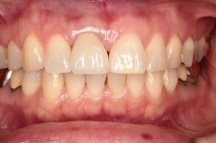

真ん中写真は部分矯正後、被せ物(保険診療・前装冠)を入れ治療終了時です。

どのくらい持つかは不明でしたので自費治療はお勧めしませんでしたが、

治療終了後10年が経過していますが、現在もよい状態が保てています!

先日の定期健診の際も、「随分持っていますね」

と大変満足されていました。